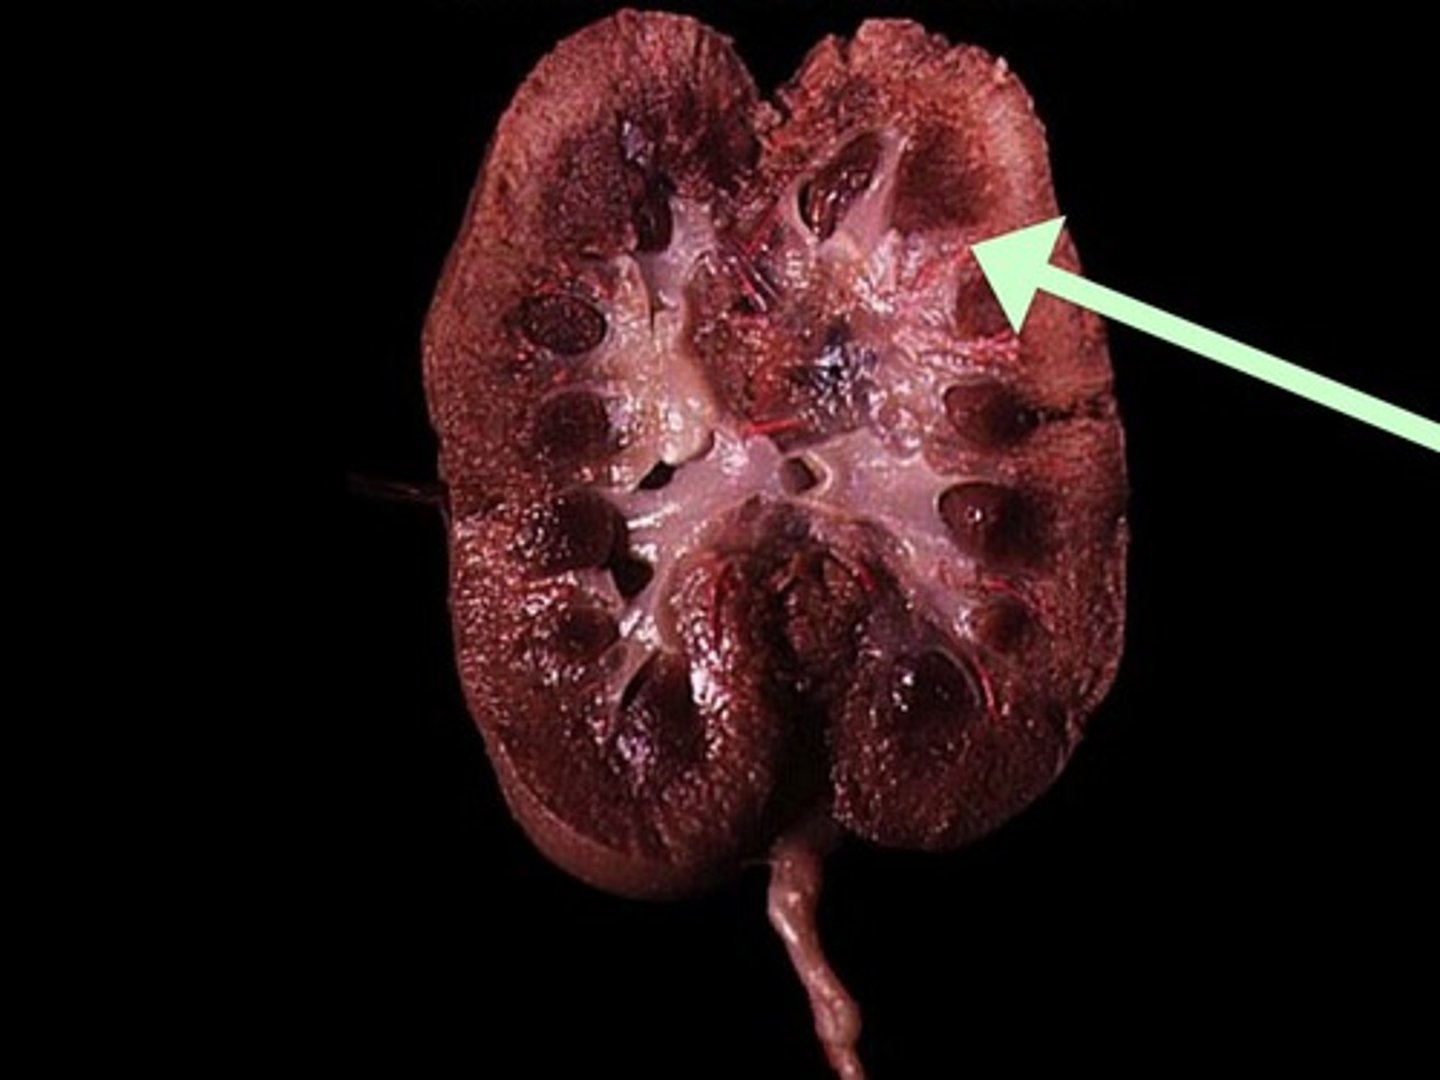

Renal Cortex

Renal Medulla

Renal Pyramid

Renal Column

Renal Pelvis

Ureter